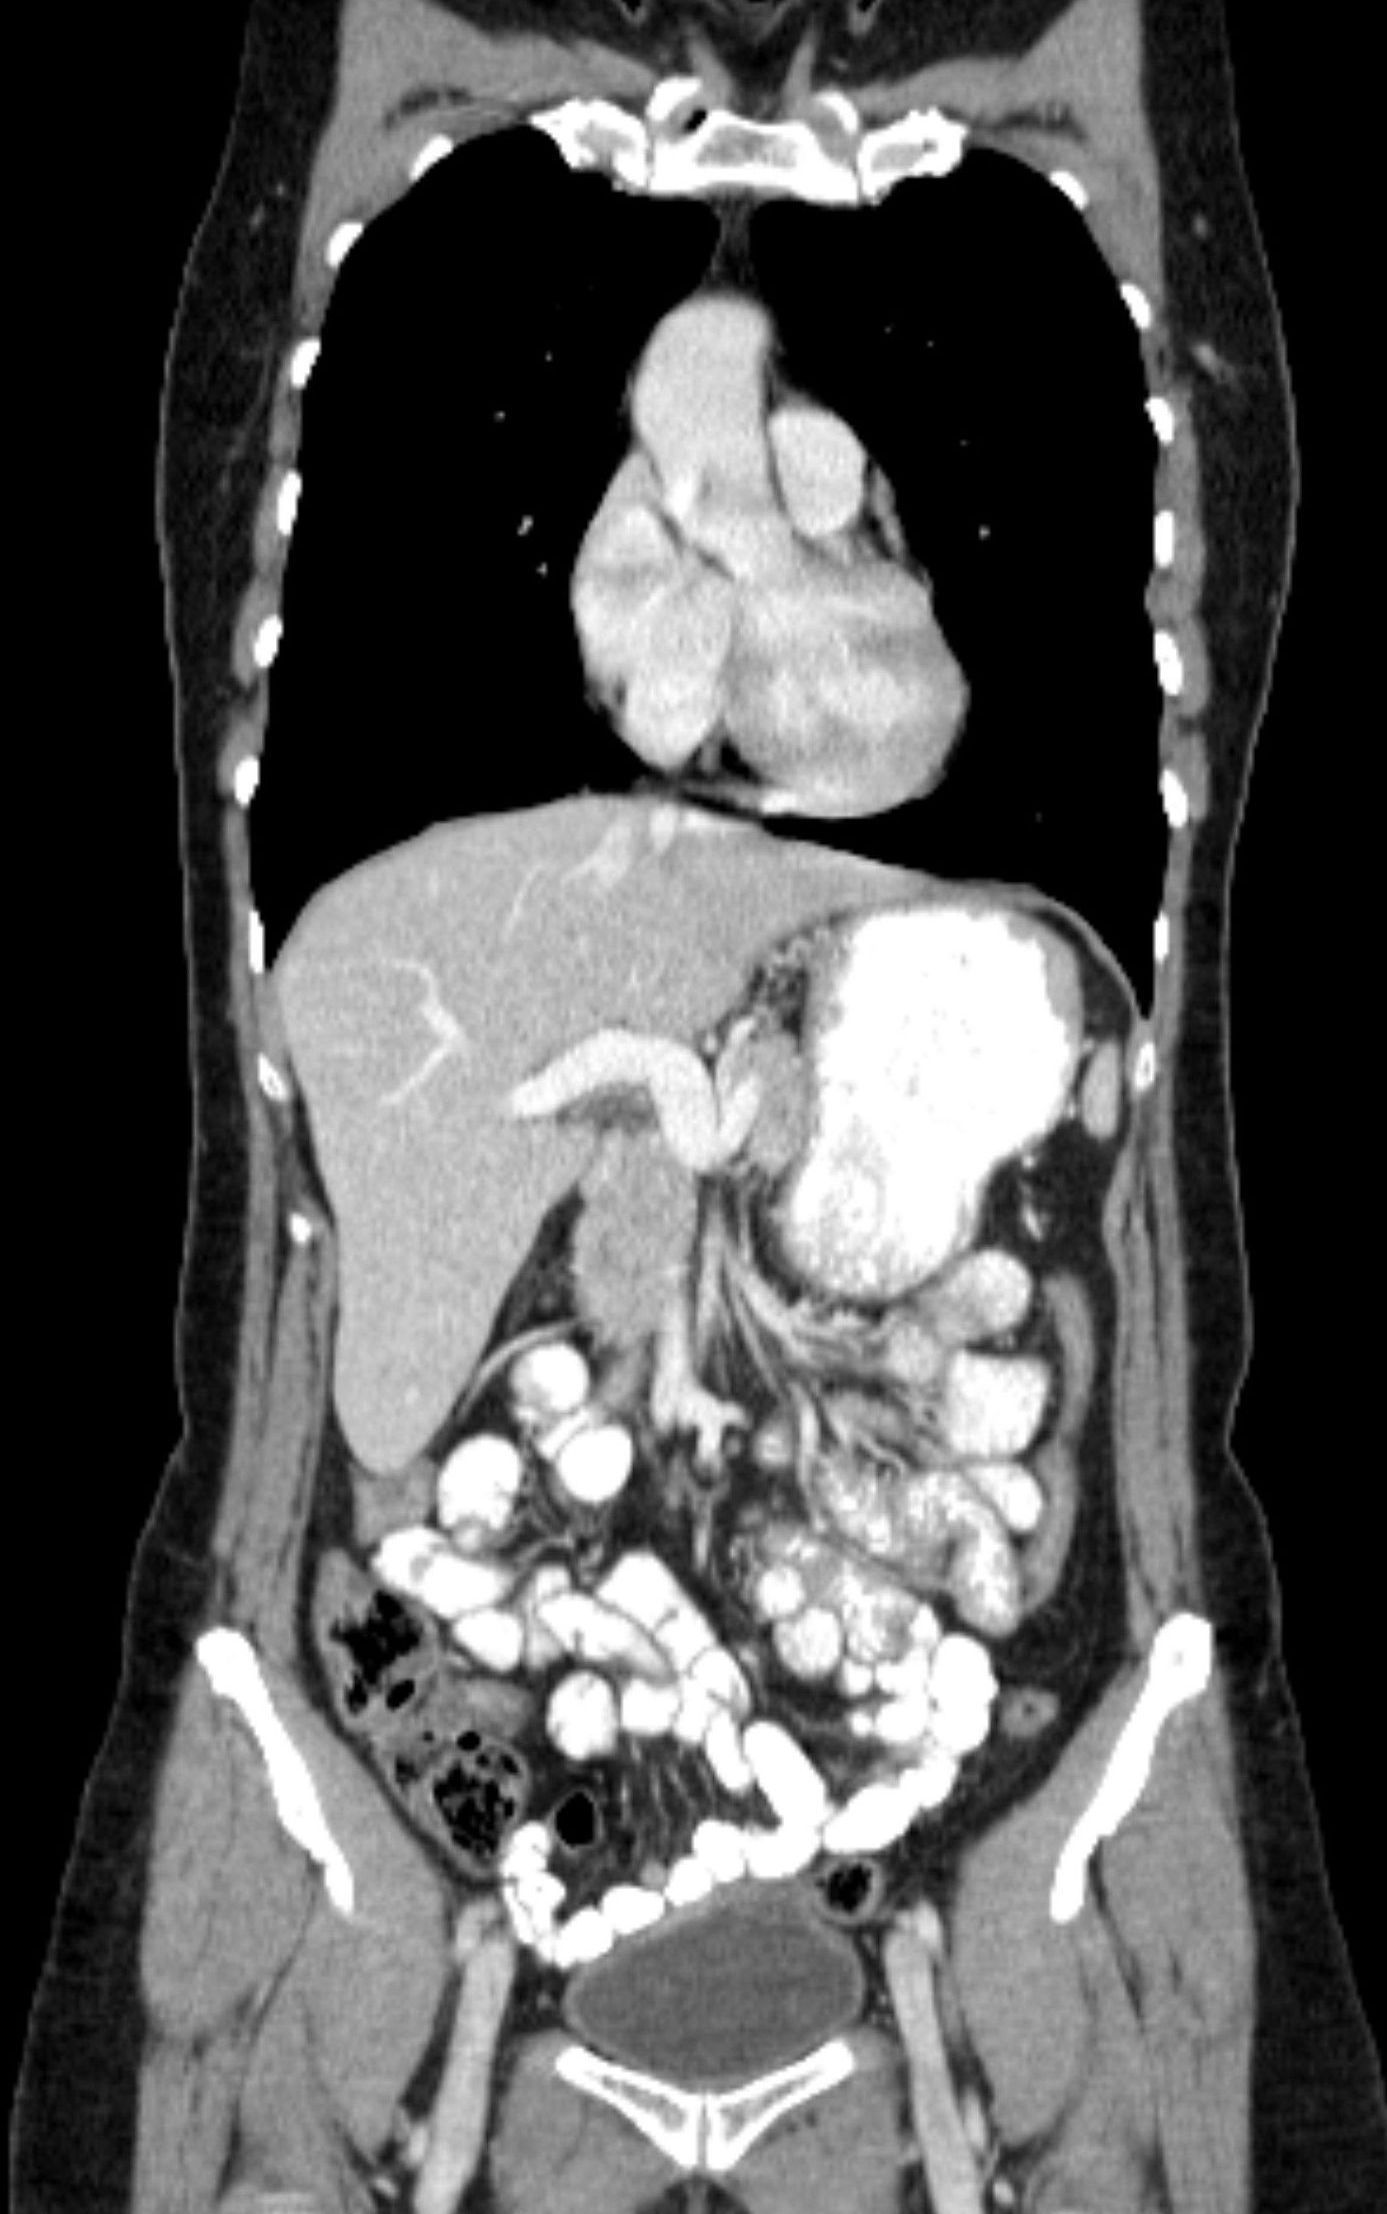

CT Abdomen

Zur Beurteilung der Bauch-organe und der Lymphknoten im Bauchraum bietet sich die Abdomen-CT an. Der Patient trinkt hierfür in der Regel Kontrastmittel zur besseren Sichtbarkeit der Darmschlingen und bekommt zur Darstellung der Organe KM gespritzt.